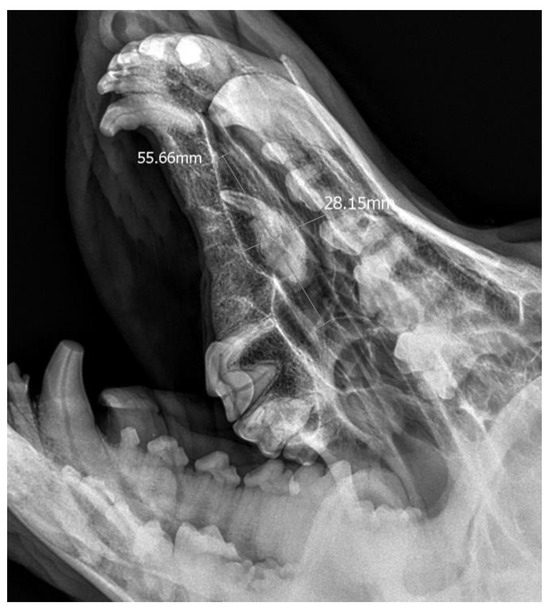

• Case 2

A 3-year-old German Shepherd dog was referred with a suspected periapical abscess of a tooth on the right side. The medical history of the pet client reported that the dog had been treated for chronic rhinitis for 6 months. On clinical examination, tooth 104 (right maxillary fang) was observed to be missing, with no wounds or fistulas in the oral cavity. Rhinoscopic examination showed features of chronic rhinosinusitis, with convexity of the nasal wall mucosa on the right side of the nasal cavity, without proliferative changes or foreign bodies. Radiological examination revealed the presence of an ectopic tooth located outside the alveolar process in the region of the maxillary cranium. Its shape was not characteristic of any normal tooth. It had a soppy crown and an incompletely formed root. The tooth was surrounded by a dentigerous cyst measuring 5.6 × 2.8 cm (Figure 5). After tooth extraction using the CLP technique and cyst lysing, the bone defect was filled with a hydroxyapatite polymer material previously soaked in 0.9% NaCl. The plasticity of the material was exploited so that it was possible to fill the bone defect with the material through a dissected bone window of 3 cm in diameter without enlarging the bone defect. A follow-up X-ray 28 days after the procedure showed normal filling of the defect with bone, without signs of inflammation or granulation formation within the jawbone. On clinical examination, resolution of nasal discharge problems and the absence of features of inflammation within the nasal cavity were observed (Figure 6).

Figure 5. X-ray in oblique head projection. The image shows an ectopic tooth along with an alveolar cyst (the dimensions of the cyst are marked).